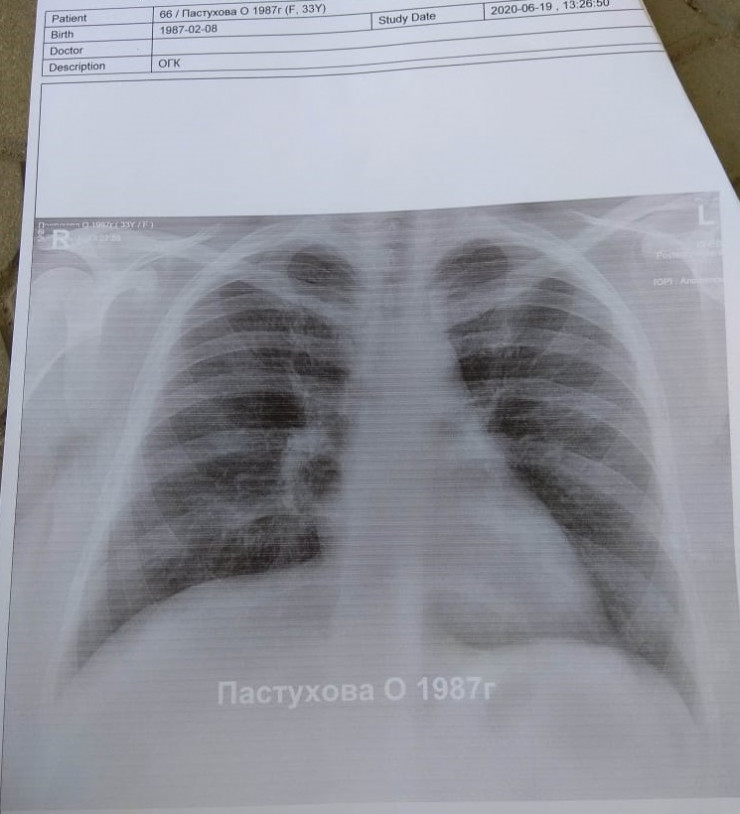

Одно хорошо: у меня муж - врач. Когда 19 июня у меня начался сильный кашель, он настоял, чтобы я сходила на рентген. Я шла по улице в маске и за версту обходила мам с младенцами на руках, не дай бог заразить кого-то! Рентген показал, что у меня бронхит. Правду говорят: "У страха глаза велики". Я, начитавшись про "матовое стекло", спрашиваю со слезами на глазах: "А что это за затемнение в левой части снимка? Легкое поражено?" Муж смеется: "Это сердце".